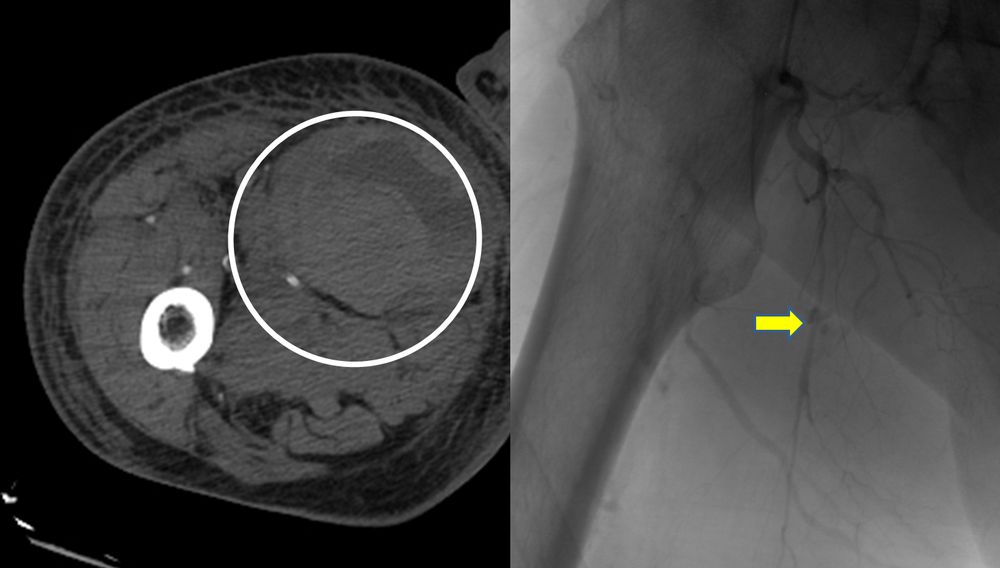

♦ Όγκους

Είτε προεγχειρητικά για την ελάττωση της αιμάτωσης του όγκου, είτε θεραπευτικά σε ορισμένες περιπτώσεις που δεν απαιτείται χειρουργείο ή υπάρχει αντενδειξη για χειρουργική αφαίρεση του όγκου.

Συνοπτικά υπό την καθοδήγηση του αγγειογράφου, αναγνωρίζεταιτο παθολογικό αγγείο-αγγεία και με ειδικούς καθετήρες και μικροκαθετήρες, διοχετεύονται εμβολικά υλικάόπως μικροσφαιρίδια ή coils, ώστε να αποφραχθεί ή να μειωθεί η παθολογική αγγείωση.